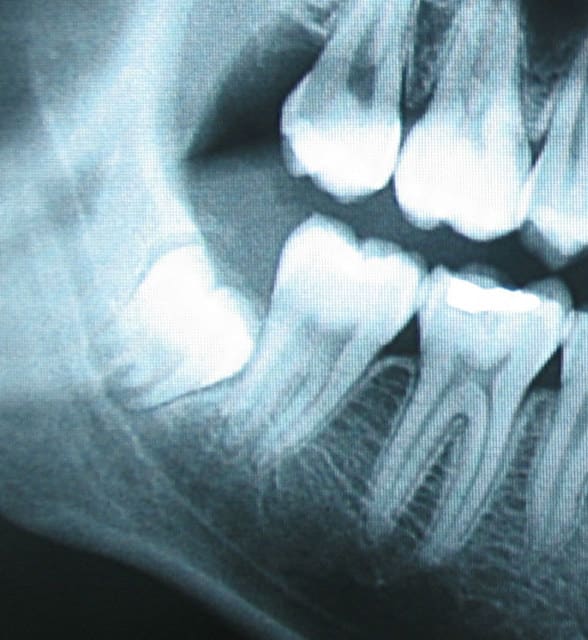

Voici une 48 et 38. Qu'est ce que tu en penses ? A laisser ou à extraire sachant qu'elles sont asymptomatiques chez une personne de 20 ans en bonne santé.

Pour tes radios, je laisserais en place.

pour canin

38 et 48 à laisser

J'avour que ce sont des extractions dites prophylactiques. On ne peut prévoir de façon absolue les complications sur ce genre de dents. Le seul truc sûr c que le contexte paro pour les 7 n'est pas idéal. De plus les extraire maintenant est beaucoup plus simple et moins risqué que dans 5 ans. Dans 5ans c sûr et certain que les racines seront de part et d'autre du nerf. J'avais quand même precrit un scanner pour info et sur la 48, les racines poussent effectivement sur le canal.

Le dernier argument c'est que le patient est jeune et qu'il va bien cicatriser avec le minimum de séquelles pour les 7.

Si les dents n'étaient pas à proximitré du nerf, je pense que je les aurait laissé.